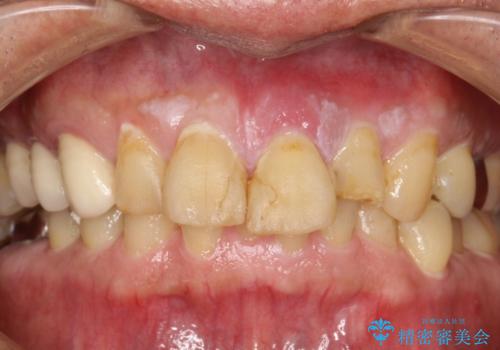

[ セラミック・インプラント全顎治療 ] 長年悩まされている歯の治療にケリをつけたい